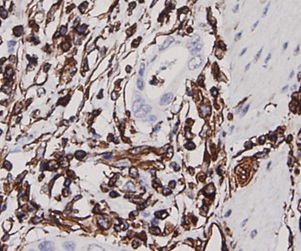

ApplicationsFlow Cytometry, Western Blot, ImmunoCytoChemistry, ImmunoHistoChemistry

- ApplicationsFlow Cytometry, Western Blot, ImmunoCytoChemistry, ImmunoHistoChemistry